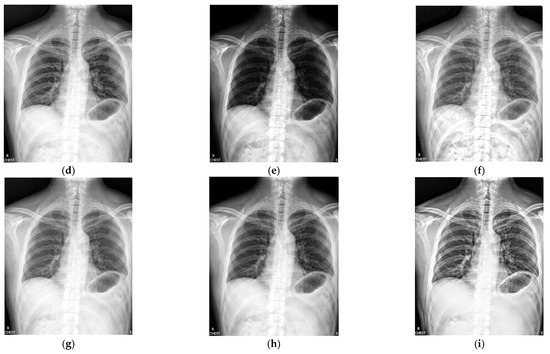

Figure 4 shows the enhancement images of eight approaches experimented on X-ray image 4. Figure 4a shows the original X-ray image 4; Figure 4b is the result computed by McCann—the image is too bright; Figure 4c depicts the image enhanced by RLBHE—the image is too dark; Figure 4d is the result achieved by RESIHE—the effect of enhancement is not obvious; the image obtained by TBCSSR is shown in Figure 4e—the image is dark; Figure 4f is the result enhanced by GDGIF—the details of the image are well preserved; Figure 4g and Figure 4h are the results enhanced by SMIPC and FuzzyII, respectively; Figure 4i is the result calculated by our approach. Table 4 shows evaluation data in Figure 4, and we can notice that the values of AG, H, ALC, SF and MG are the best.

Figure 4.

Comparison on X-ray image 4. (a) Original image; (b) McCann; (c) RLBHE; (d) RESIHE; (e) TBCSSR; (f) GDGIF; (g) SMIPC; (h) FuzzyII; (i) Proposed method.